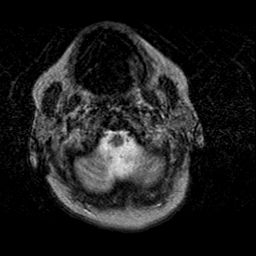

Creutzfeld-Jakob disease: T2-weighted MR -- Slice #0

[Home][Help][Clinical] Slice 0